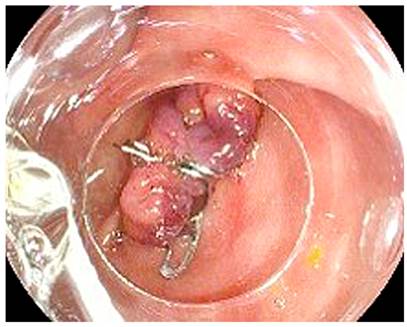

Percutaneous drainage of the collection was performed by interventional radiology and drainage catheter placement, in which 150 mL of purulent and intestinal contents were obtained, thus, controlling the infectious process and optimizing the patient’s clinical condition. Based on the intraoperative findings and the laterolateral gastrojejunostomy, 3 days after the percutaneous drainage, the patient underwent endoscopic treatment of the proximal jejunal fistula through pyloric exclusion to reduce intraluminal content flow through the affected loop, concomitantly with multimodal pharmacological management with proton pump inhibitor (PPI), opioid, antidiarrheal, and parenteral nutrition. Given the patient’s comorbidities and trying to find the least invasive procedure, the Ovesco device was used to perform the pyloric exclusion, considering an appropriate functionality of the gastrojejunostomy, which was technically successful (Figure 3).

The stomach was explored up to the pylorus, where an abundant gastric mucous lake and permeable gastrojejunostomy on the anterior wall were observed, the pylorus was identified, and using a suction technique, the edges of the pylorus were tackled with an Ovesco 12/6 GC clip. A permeable angle was observed during the examination, so the second Ovesco 12/6 GC clip was placed, occluding the pylorus in its entirety as part of the indicated pyloric exclusion.